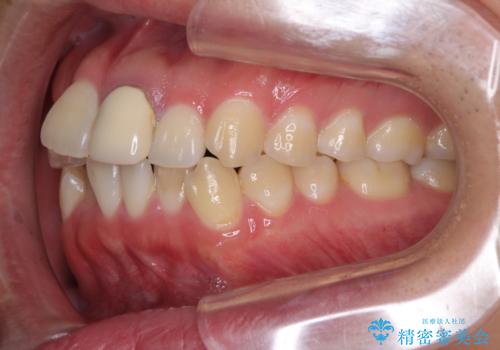

前歯の歯並びとクラウンを改善 インビザラインとオールセラミック

- 前歯の歯並びと不自然な色をした前歯のクラウンを気にして来院された患者様です。

上下前歯の歯列不正はインビザラインにより歯列を整え、その後に、前歯をオーダーメイドタイプのオールセラミッククラウンにて補綴治療することとしました。

初診時には、歯並びを整えることのみを検討されていましたが、歯列が整うにつれて不自然な色合いが気になるようになり、矯正治療を行ってから補綴治療をする計画を受け入れてくださいました。

口元の印象が明るく変わり、患者様には大変満足していただきました。